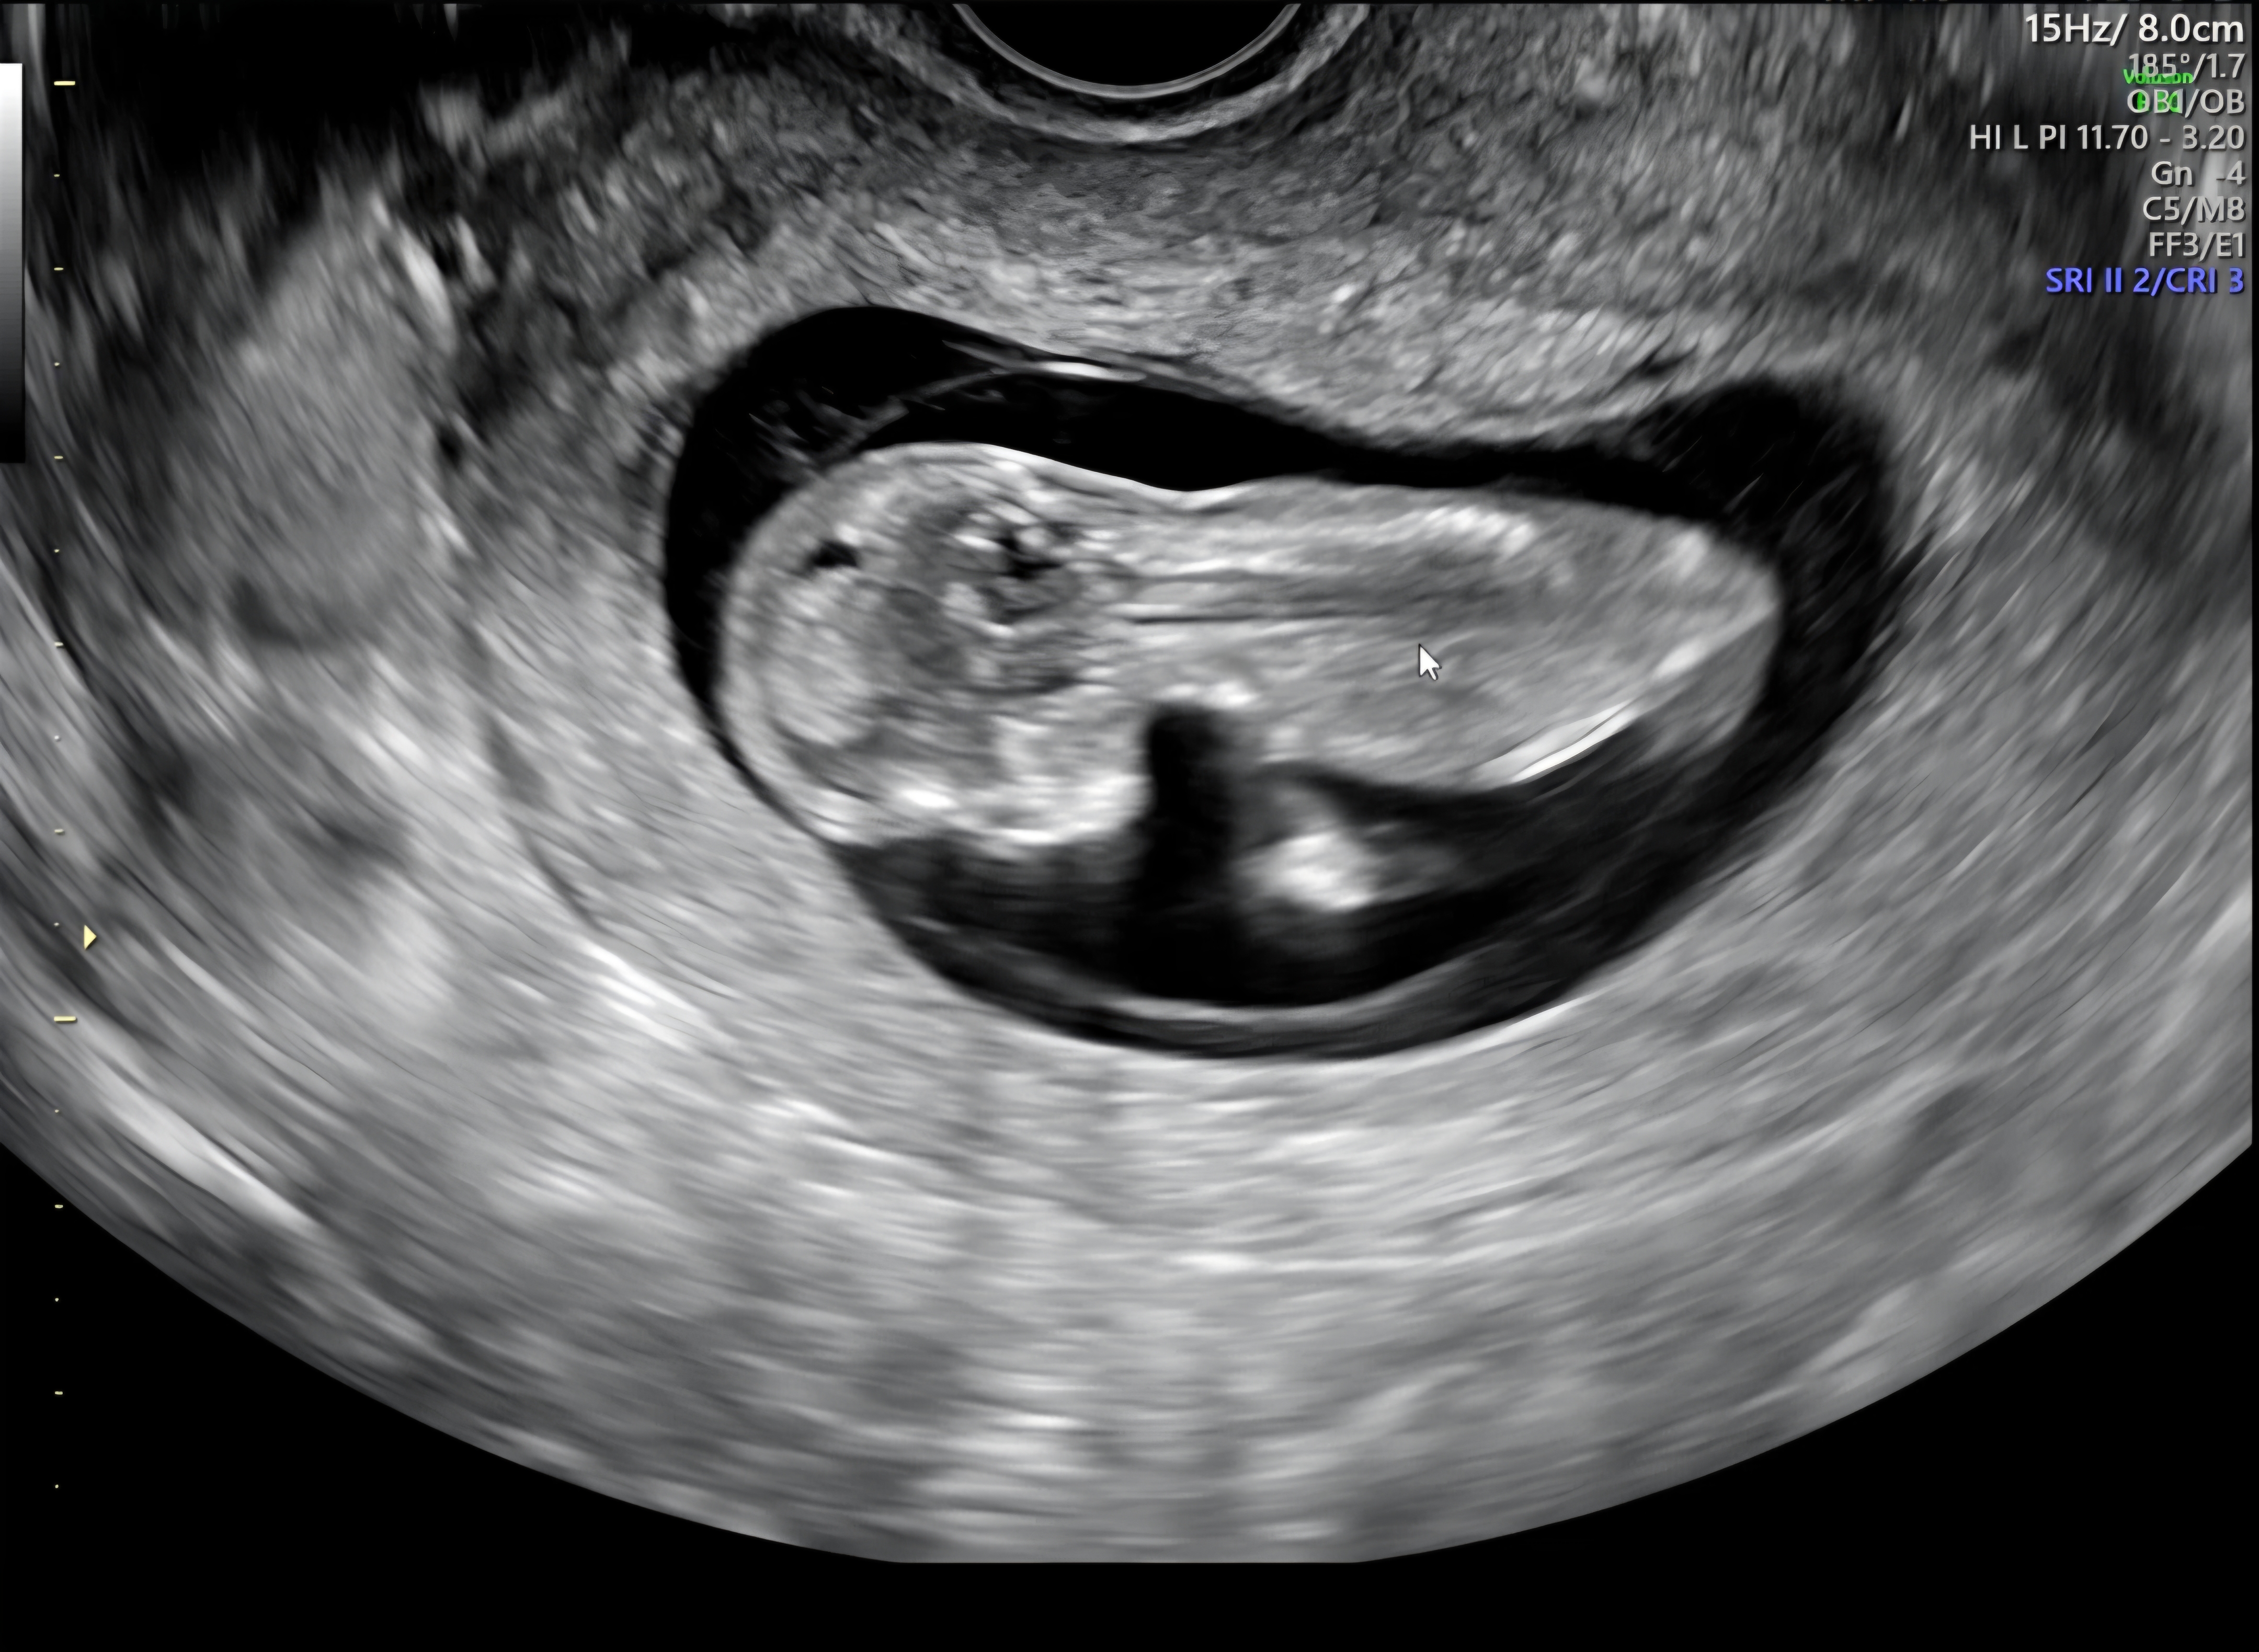

초음파 사진 완료